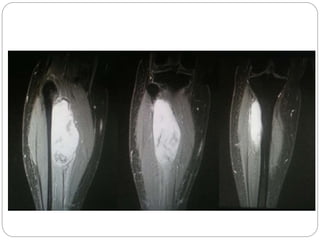

This document discusses 8 oncology cases. Case 1 involves a 40-year old female with right knee pain. Case 2 is a 28-year old male with a left subtrochantric fracture from a MVA who is now experiencing increasing left knee pain and swelling. Biopsy results showed high-grade osteosarcoma. Case 3 is a 30-year old female with breast cancer and bone metastases causing bilateral hip pain.